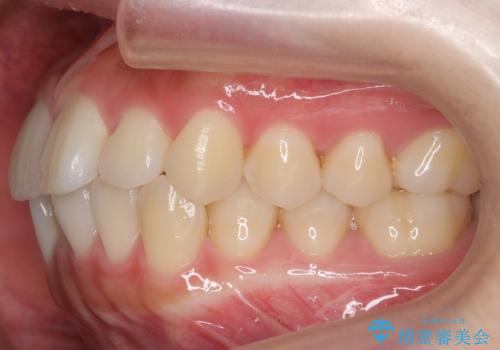

インビザライン モニターで前歯をきれいに

- 前歯のがたつきをきにされていました。

上下の前歯をやすりがけする処置(IPR)を行い、前歯の並びを出っ歯にしないようにしながら整えました。

症状が軽度であるためモニター採用になりました。